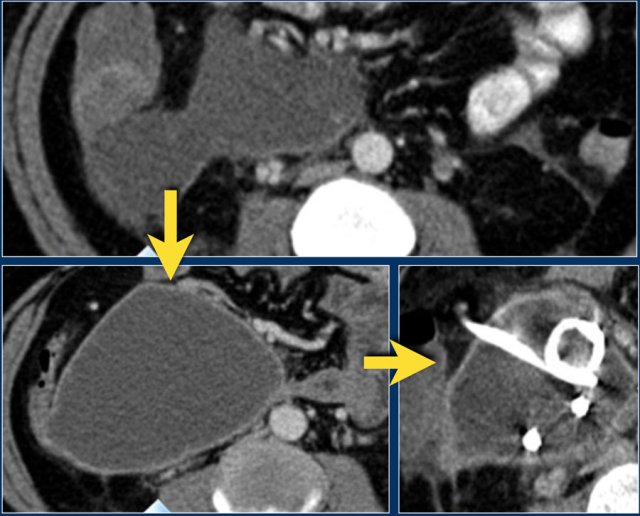

The images are of a patient with acute pancreatitis.

On the upper image is a collection in the area of the pancreatic head in the right anterior pararenal space.

At this stage, it is not possible to distinguish between an acute peripancreatic fluid collection and acute necrotic collection.

On a follow-up scan the collection in the right anterior pararenal space increased in size.

It has fluid density and a thin enhancing wall.

This can be a pseudocyst or walled-off-necrosis and it may or may not be infected.

The patient became septic and a percutaneous drainage was performed.

After drainage the collection barely diminished in size.

The patient underwent surgery and the collection was found to consist of necrotic debris, which was not appreciated on CT, hence this was a walled-off-necrosis and not a pseudocyst.

The necrotic debris was too viscous for successful percutaneous drainage.